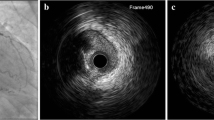

NIRS for coronary imaging is currently available as a combined NIRS/IVUS imaging system (TVC Imaging System TM, InfraRedx Inc, Burlington, MA) that consists of a 3.2-Fr catheter, a pullback and rotation device, and a console, which houses the scanning laser, the computer that processes the spectral signals, and two monitors [4]. The catheter tip emits and collects light, which is transmitted back to the system for processing. The catheter imaging core is able to collect data rapidly by rotating at 960 rpm as it is pulled back at an automated speed of 0.5 mm/s. IVUS images are simultaneously acquired and inherently co-registered with NIRS measurements and are available in various combined and individual displays. The IVUS transducer operates at 40 MHz. A NIRS/IVUS catheter that acquires “high-definition” IVUS images using a 50 MHz transducer is in clinical use at several sites in the USA.

Spectral data are automatically analyzed by the system to produce a digital color map of the vessel wall, called a chemogram, which represents the probability of the presence of LCP over the scanned segment of vessel (Fig. 1). The NIRS algorithm that generates the chemogram was trained using histopathology as the gold standard for lipid identification and a rigorous experimental methodology that included blinded, prospective validation under simulated clinical use conditions [5]. It is notable that despite widespread claims of lipid core detection capability by other methods (such as OCT, grayscale IVUS, and radiofrequency IVUS), to date, no other technology has been subjected to a rigorous validation in this manner, and none has an associated FDA label claim as NIRS does. The algorithm for LCP detection in humans was constructed defining LCP as a fibroatheroma containing a lipid core ≥200 μ thick and >60° angular extent on histologic analysis. The algorithm could reliably identify LCPs with an area under the curve of 0.80 [5]. The NIRS algorithm was prospectively validated in humans in the SPECTACL study, in which chemograms obtained in vivo were similar to those obtained in histology controls [4]. The results of these studies led to FDA approval of the NIRS imaging system in 2008 for LCP detection. In 2010, the FDA approved the addition of IVUS to the NIRS system.

On the chemogram, each pixel is assigned a color (128-color scale) based on the probability that lipid is present at that site, with the color scale transitioning smoothly from red (zero probability of LCP) to yellow (100 % probability of LCP). The color scale transition from red to yellow occurs near a probability of 0.60. Pixels with indeterminate data, such as those interfered with by the guidewire, may appear black. On a longitudinal chemogram, the pullback location in the vessel is denoted on the x-axis and the circumferential position on the y-axis. The lipid core burden index (LCBI) is a measure of lipid burden for a given vessel segment, calculated by dividing the number of yellow pixels (p > 0.6) by the total number of valid pixels in that segment, multiplied by a factor of 1000 (LCBI range 0–1000) [6]. The maxLCBI4 mm is defined as the LCBI of the 4-mm region with the highest lipid burden within the segment of interest [9].

The block chemogram is a summary measure that allows rapid interpretation as well as potential traceability back to the autopsy validation. Each block corresponds to a 2-mm segment of the pullback, and the color corresponds to the 90th percentile probability for the pixels within that segment. Thus, the block color represents probability of lipid within the segment, as follows: yellow P > 0.98, tan 0.84 ≤ P ≤ 0.98, orange 0.57 ≤ P < 0.84, and red P < 0.57 [9]. Other intuitive and potentially important parameters can be computed, such as the LCBI for selected regions of interest, or the lipid arc, which is the number of degrees spanned circumferentially by the lipid at a given longitudinal location.